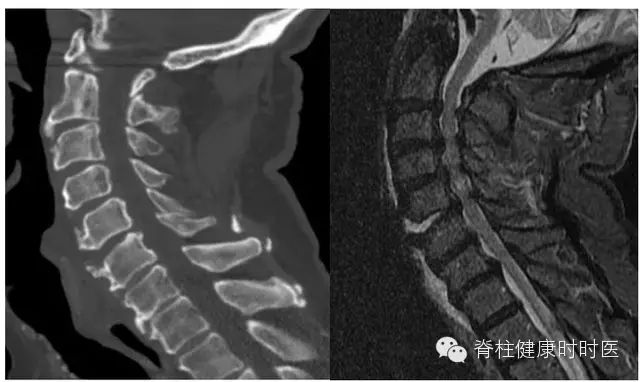

100例患者(205处骨折)MRI检查提示骨髓水肿。对骨折进行分类后再分析,骨折类型与骨髓水肿密切相关,92例患者的188处压缩骨折,与骨髓水肿及程度相关。齿状突骨折 42 例,基本没有骨髓水肿(图 1)。12 例经椎间和 / 或邻近终板的骨折,亦无骨髓水肿(图 2)。10 例强直性脊柱炎患者,经椎间 - 终板或椎体的骨折,骨髓水肿有限或没有(图 3)。6 例 Chance 骨折,均无骨髓水肿(图 4)。

图 1 新鲜齿状突骨折。左图:矢状位 CT 示颈椎 III 型齿状突骨折;右图:短时间反转恢复序列 MRI 示齿状突和 C2 无骨髓水肿。棘突间韧带 T2 相高信号,证实韧带损伤和椎前水肿。